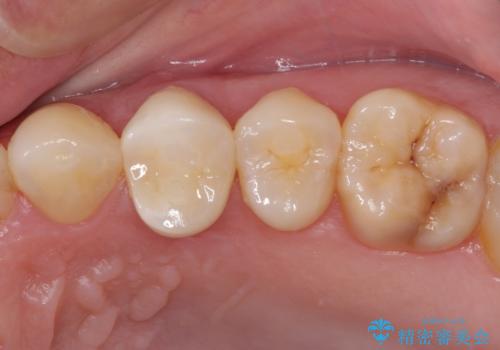

【根管治療】噛んだ時にしみる。最近になってズキズキ痛み、長引く痛みがある

担当医 河口智英